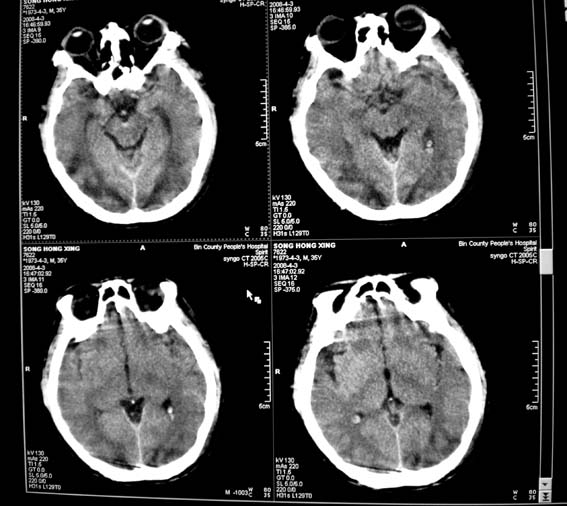

标题: CT12659:头外伤,现昏迷。 [打印本页]

标题: CT12659:头外伤,现昏迷。

10天前,头、胸、腹及腿部外伤,当时有蛛网膜下腔出血,肺挫伤,肝脾破裂,腿部骨折,近两天昏迷。

sah,dai,双枕顶叶外伤性脑梗死。dai的受伤机制是脑的瞬间旋转作用和脑内剪切力所致。临床表现为昏迷出现早,昏迷程度深,昏迷持续时间长,恢复不完全。ct表现为脑白质区散在的局灶出血点,颅内高压表现不明显。